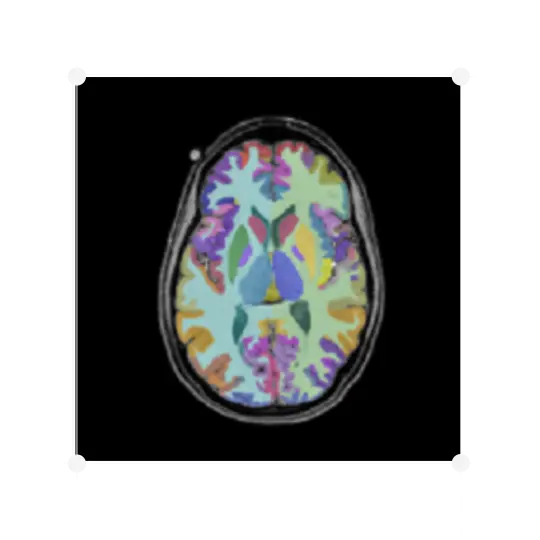

Changes in brain volume, or atrophy, are among the most established effects of many neurodegenerative diseases. IXICO have been providing volumetric analysis for late-phase trials for our partners for more than 12 years, measuring brain volume both cross-sectionally and longitudinally using our LEAP (Learning Embeddings for Atlas Propagation) pipeline, which provides the following measures:

• Global – making measurements on the whole brain

• Regional – measuring specific local brain regions

IXICO also cover a range of volumetric solutions, including Freesurfer, MIDAS BSI and synthSEG.

IXICO's proprietary deep-learning platform, IXI™ can provide highly accurate automated segmentations of the caudate, putamen, thalamus, whole brain and lateral ventricles. For the caudate, whole brain and ventricles, the IXI™ Platform’s segmentations are then combined with an updated version of the Boundary Shift Integral (BSI) algorithm, the generalised BSI (gBSI; Prados et al. 2015).